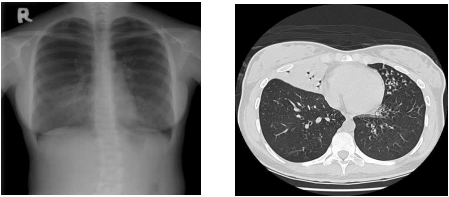

73 一位 20 歲女性,主訴胸痛和咳嗽,胸部影像如附圖,則最可能的診斷為下列何者?

(A)右肺上葉肺炎 (B)右肺中葉肺炎 (C)前縱膈腔腫瘤 (D)右肋膜局限性積液

74 一位 53 歲女性,因左乳癌接受化療,主訴衰弱及呼吸急促,注射對比劑後 CT 影像如附圖,則最可 能的診斷為下列何者?

(A)肥厚性心肌病變 (B)心包膜積液 (C)擴張性心肌病變 (D)縱膈腔淋巴結轉移